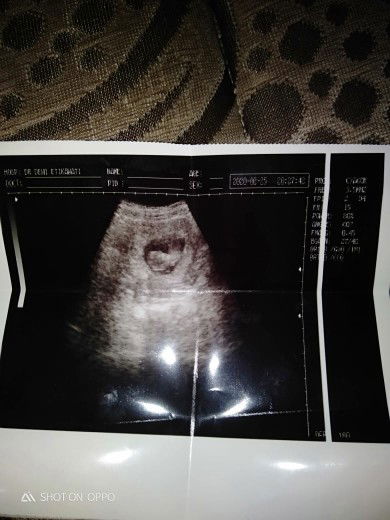

bun ini hasil usg kira" udah brapa usia kandungan ny

Bun ini hasil usg kira" sudah brp usia kandungan saya